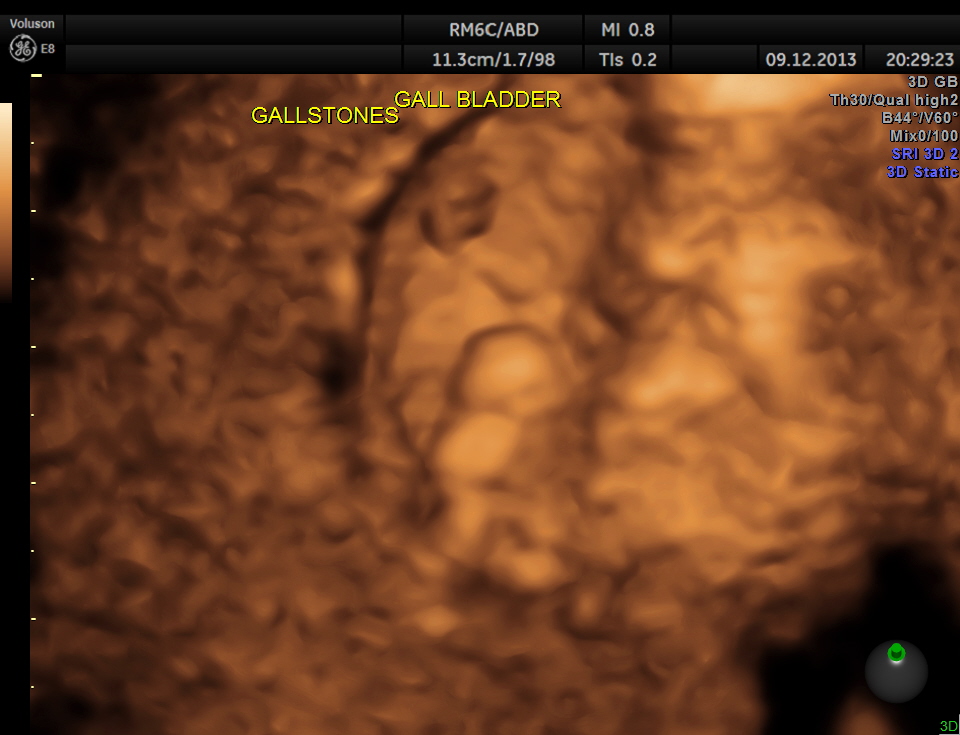

3 d of the same is given below.

Usually the patient and the surgeon are interested in knowing the number of gallstones . I always have felt that the number would not matter . But is there a difference between 2D , 3D and more advanced high-definition rendering ? Please decide for yourself.